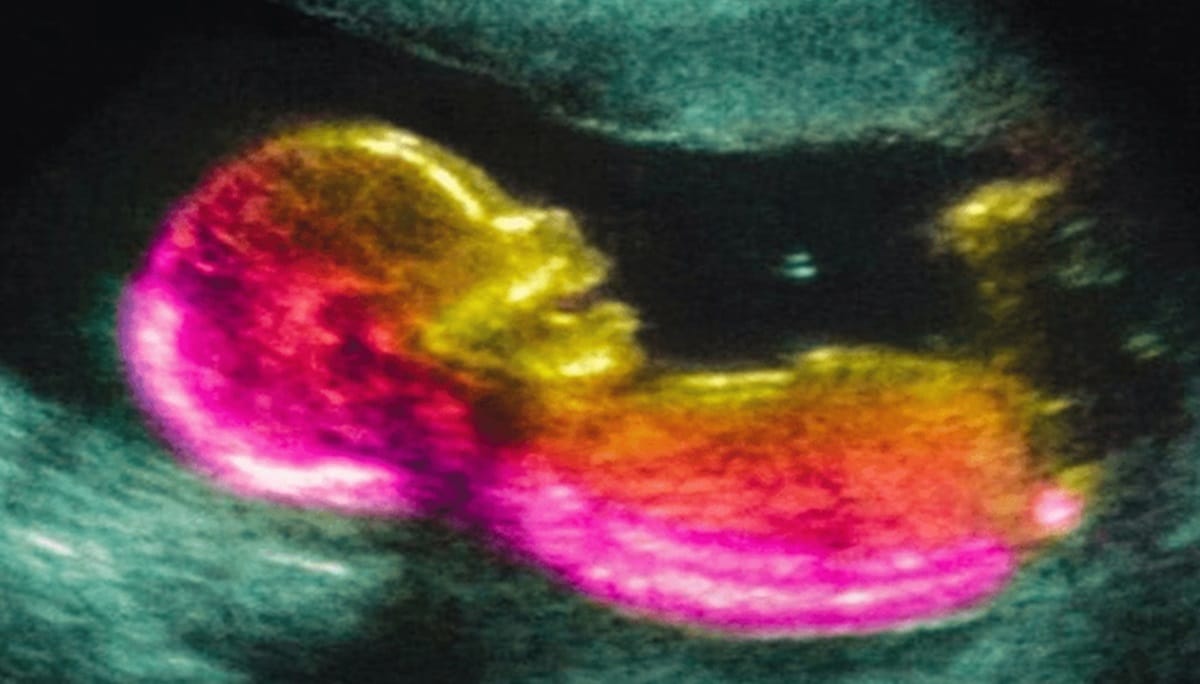

Uma pesquisa dos Estados Unidos voltou a colocar a gravidez no centro das discussões sobre o transtorno do espectro autista. O foco, desta vez, está no intestino materno.

Cientistas observaram que alterações na microbiota de fêmeas grávidas foram acompanhadas por um aumento de uma substância inflamatória chamada IL-17A, e isso afetou o desenvolvimento cerebral dos filhotes em testes com camundongos.